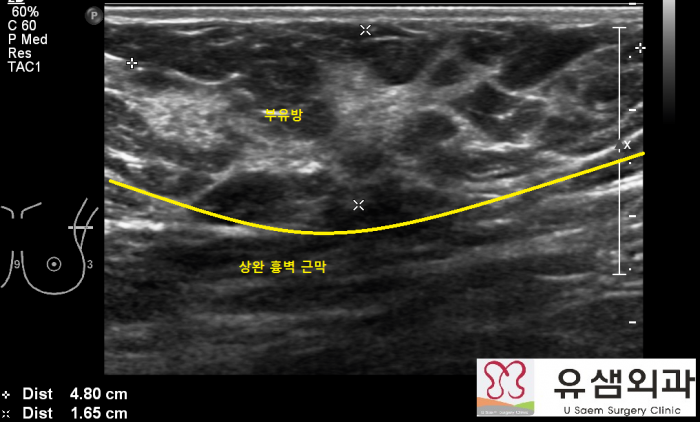

¼ö¼ú Àü ºÎÀ¯¹æÀÇ À§Ä¡¿Í °Üµå¶ûÀÌ µ¿Á¤¸ÆÀÇ À§Ä¡¸¦ ÃÊÀ½ÆÄ¸¦ ÀÌ¿ëÇÏ¿© ÆÄ¾ÇÇÑ ÈÄ ¸¶Å·

ÆæÀ¸·Î Ç¥½ÃÇÕ´Ï´Ù. ±× ÈÄ ºÎÀ¯¹æ À§¿¡ Àû´çÇÑ Å©±âÀÇ Àý°³Ã¢À» Ç¥½ÃÇÕ´Ï´Ù.

¼ö¼ú Áß ÃÊÀ½ÆÄ·Î ºÎÀ¯¹æÀÇ ¹üÀ§¸¦ ÆÄ¾ÇÇÑ ÈÄ¿¡ »ó¿Ï È亮 ±Ù¸·À» È®ÀÎÇϰí, ±Ù

¸· ÁÖº¯°ú ºÎÀ¯¹æÀÇ Áö¹æ ºÎºÐ¿¡ ±¹¼Ò¸¶ÃëÁ¦(Æ©¸Þ½¼Æ®¿ë¾×À» »ç¿ëÇÏ¿© ¾ÆÁÖ Å«

ºÎÀ¯¹æµµ ±¹¼Ò¸¶Ãë·Î ÀýÁ¦ÇÒ ¼ö ÀÖ½À´Ï´Ù.)¸¦ ÁÖ»çÇÕ´Ï´Ù.

¼ö¼ú Áß »ó¿Ï È亮 ±Ù¸·ÀÌ ºÎÀ¯¹æÀÇ ¾Æ·§ÂÊ °æ°è¸¦ ³ªÅ¸³»±â ¶§¹®¿¡ ±Ù¸·À» Àý

°³ÇÏÁö ¾Ê°í ºÎÀ¯¹æÀ» ÀýÁ¦ÇÏ´Â °ÍÀÌ Áß¿äÇÕ´Ï´Ù. ¸¸¾à ±Ù¸·À» Àý°³ÇÏ°í ±× ¾Æ